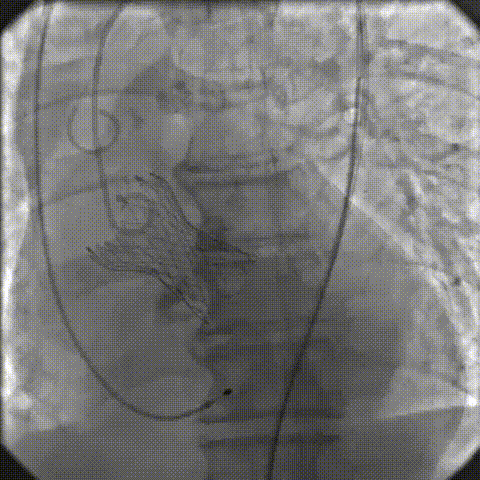

手术影像记录

主动脉根部造影

18mm球囊预扩

过弓、跨瓣

零位定位

工作位造影

缓慢脱钩

23mm球囊后扩

后扩后造影:无漏